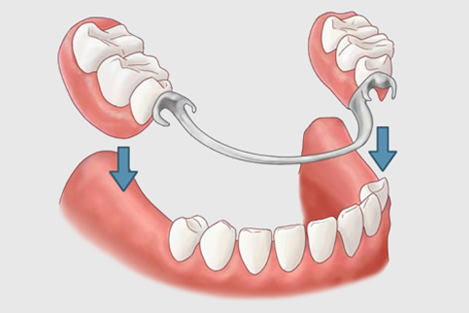

6. Removable teeth

A removable partial denture (RPD) is a denture for a partially edentulous patient who desires to have replacement teeth for functional or aesthetic reasons and who cannot have a bridge (a fixed partial denture) for any number of reasons, such as a lack of required teeth to serve as support for a bridge (i.e. distal abutments) or financial limitations. This type of prosthesis is referred to as a removable partial denture because patients can remove and reinsert it when required without professional help. Conversely, a "fixed" prosthesis can and should be removed only by a dental professional.